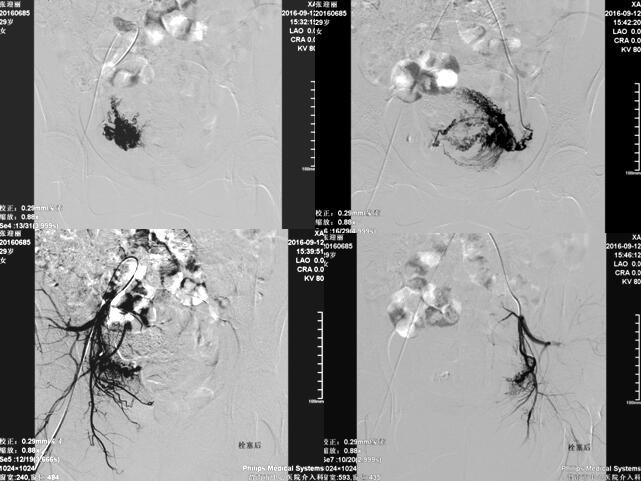

渭南市中心医院介入科在李建国主任带领下自2006年开展子宫肌瘤栓塞术,现已完成数百例相关疾病介入治疗,为渭南地区及各县患者提供了全新的子宫肌瘤治疗方法,避免患者子宫全切。子宫肌瘤栓塞术是一种安全有效的治疗方法,是由介入医生经病人腹股沟股动脉导入一导管至肌瘤的血供(子宫动脉)处,释放一些细微颗粒,弹簧圈、或者球囊等阻断肌瘤的血供、供养及出血部位,使肌瘤纤维化,出血停止,肌瘤萎缩。所有经过介入治疗的患者术后大约3-6个月相关症状完全消失。

经子宫动脉栓塞术还可应用于子宫腺肌症、胎盘植入、瘢痕妊娠、前置胎盘及产后大出血等疾病,以下为一例产后大出血患者介入治疗图片: